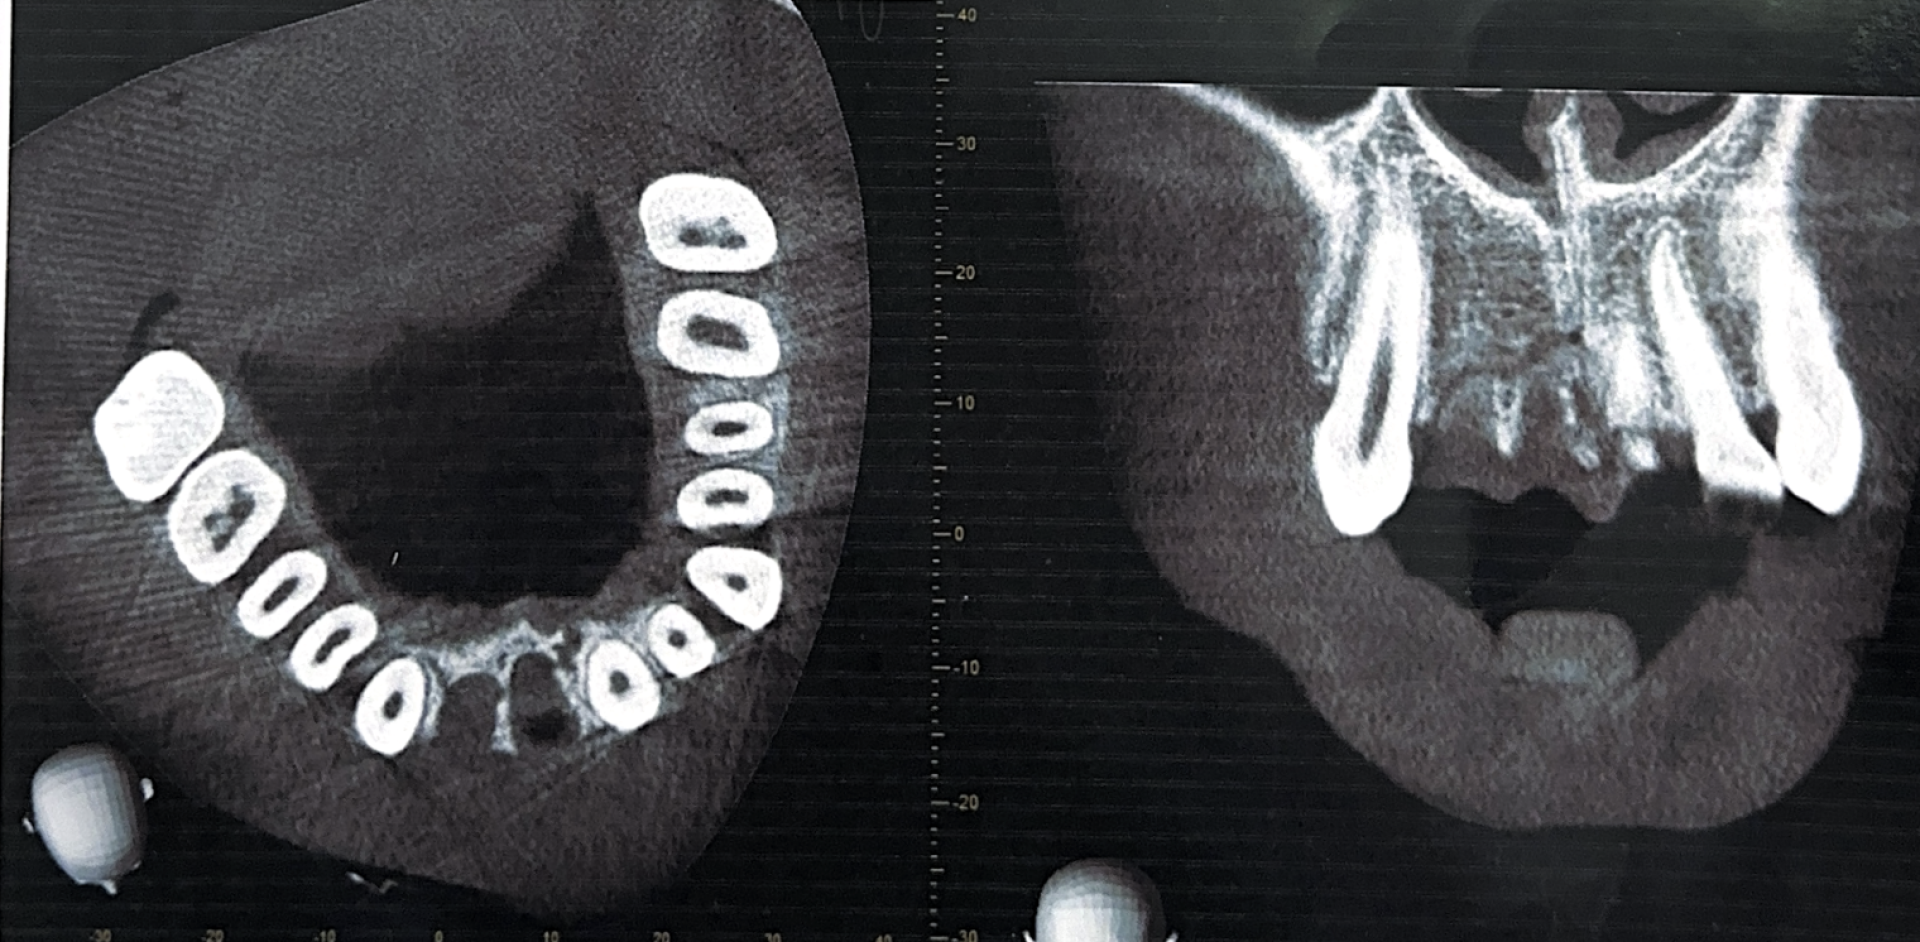

"Ему выбили 2 передних зуба с корнями сверху, оказались повреждены и раздроблены 3 нижних зуба. Один зуб внизу висел и был сломан под корень, разорвана губа насквозь, травмировано нёбо — потребовалось хирургическое вмешательство. Ребёнок был экстренно госпитализирован".

снимок зубовСнимок предоставлен семьей пострадавшего

В феврале и в марте школьник проходил длительное лечение: со слов матери, подросток перенёс операции, ему восстанавливали зубы. Весь февраль он не мог нормально есть — питался через трубочку, с трудом передвигался и не ходил в школу около месяца.

Сейчас пострадавшему требуется длительное и дорогостоящее лечение у ортодонта (брекеты, капы), а в дальнейшем понадобится имплантация. Подросток будет жить без передних зубов ещё 4–5 лет.